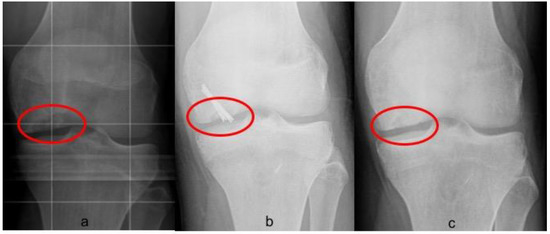

Postoperative radiographs and MRIs were used to classify and assess the healing of the treated lesion according to previously delineated criteria. (Figure 1, Figure 2 and Figure 3) A fluid interface between the OCD fragment and the condylar bone was considered a sign of incomplete consolidation. Then again, sclerosis or necrosis of the fragment were considered sign of non-consolidation [10,11].

Figure 1. Radiographic union of grade III Osteochondritis dissecans (OCD) of 2.3 cm2 in the medial condyle of left knee fixed with two Herbert screws. (a) Preoperative evaluation on anteroposterior (AP) view; (b) two months postoperative X-ray, not complete union was appreciable; (c) six months postoperative X-ray showing a complete union.